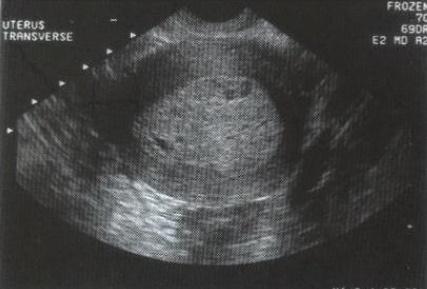

Adenomyosis

Glándulas de tejido endometrial que crecen en el miometrio

Visto en mujeres luego de los 40 años

Por sonografía: Útero Grande e hipoecoico

especialmente durante

la menstruación.